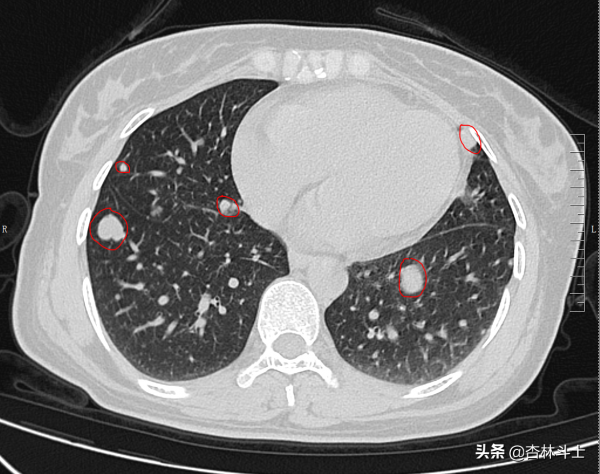

磁共振表現並結合患者病史體徵,考慮患者左側大腿上部巨大腫塊為惡性軟組織肉瘤,遂安排了頭顱3T磁共振增強及胸部CT平掃、腹部CT平掃+增強。結果胸部CT平掃部分影象如下:

圖中紅圈內為大小不等軟組織腫塊,結合既往檢查,考慮腫瘤血行播散至肺部,導致肺內多發轉移瘤。